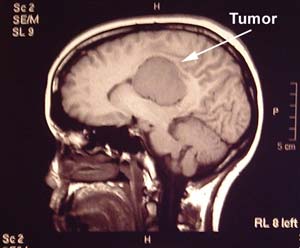

avenjers71 (7) گزارش تخلف تومور مغزی و راهکارهای درمان آن تومور مغزی عبارت است از رشد یك توده غیرطبیعی در مغز كه امكان دارد خوشخیم یا بدخیم باشد.یك تومور خوشخیم مغز ممكن است به اندازه یك تومور بدخیم ناتوانی ایجاد كند، مگر این كه به طور مناسب تحت درمان قرار گیرد.● علایم شایع تومور مغزی به شرح زیر میباشد:سردردی كه با دراز كشیدن بدتر میشود، استفراغ همراه با... 11 0 0 57 5 سال پیش